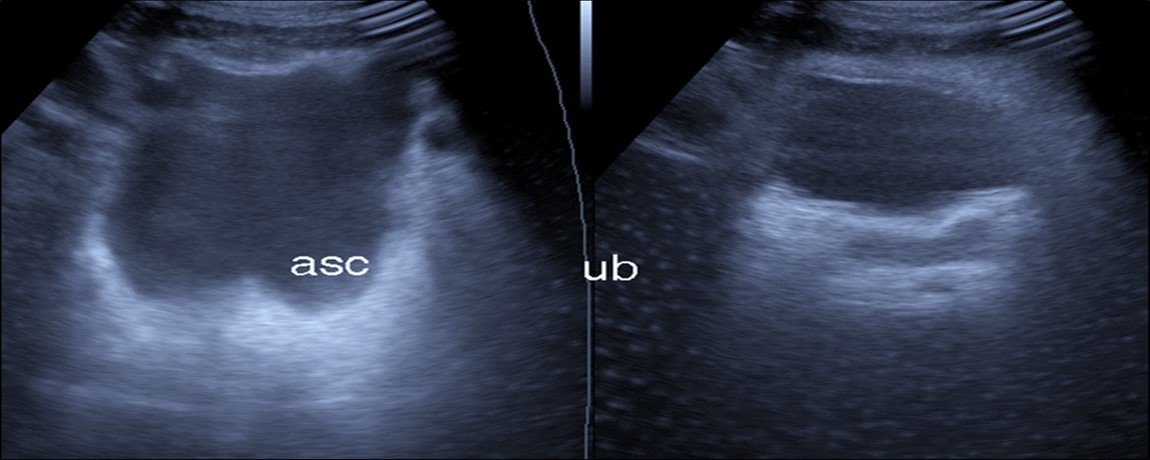

Abdominal ultrasound may revealed any of the followings:-Mild hepatomegaly with echogenic parenchyma and ascites in cases with hepatic impairment (Figure 4, Figure 5) ,thick walls of gall bladder with mildly dilated Common bile duct suggesting of biliary stasis and cholecystitis (Figure 6) .Abnormal renal echogenicity (Figure 7), suprarenal gland enlargements with heterogeneous texture ,splenic wedge shape area of hypoechogenicity ,thickened walls of bowel mainly the rectosigmoid region ,dilated bowel loops with free peritoneal fluid, and gases in the bowel wall with mesenteric and portal vein gases suggesting of bowel wall infarction13.

Figure 6.Real time ultrasound showing free ascites (asc) in patient with Covid-19.